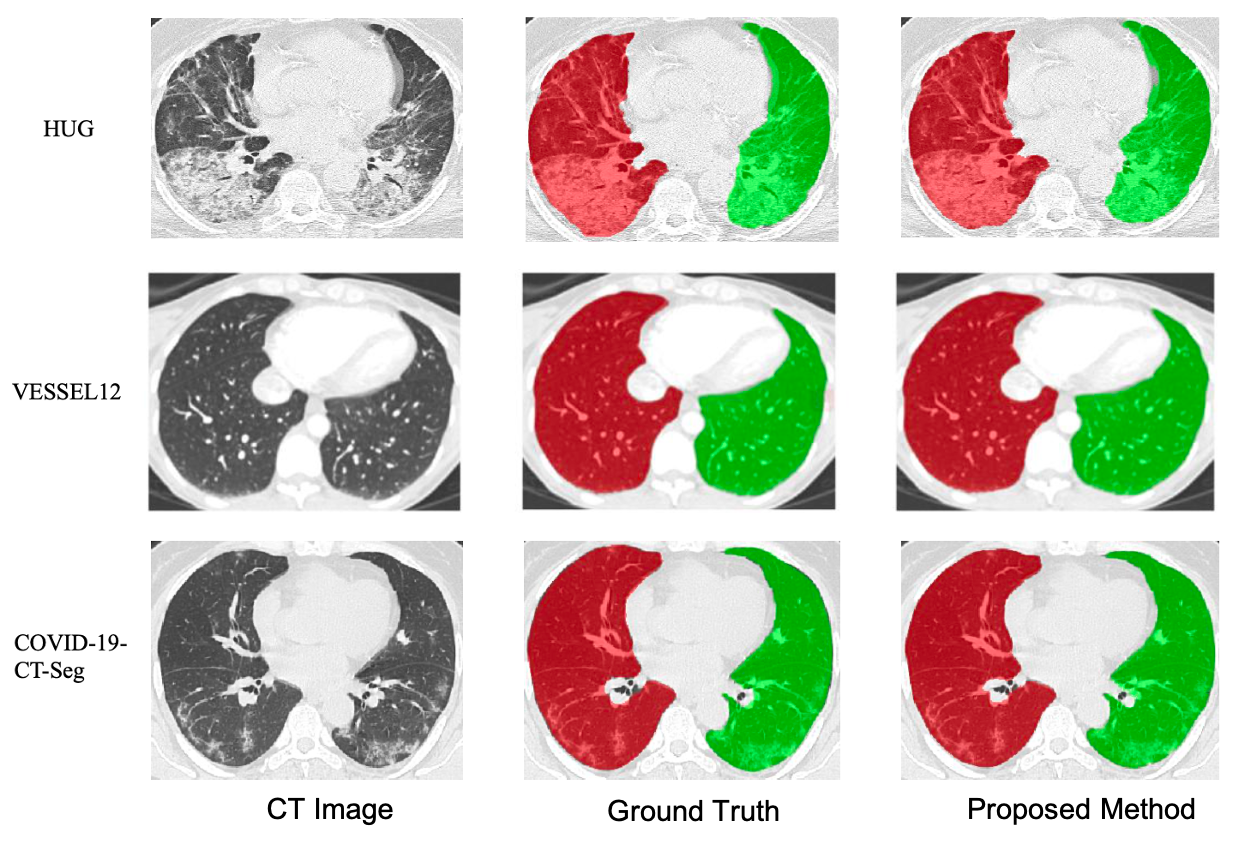

Lung segmentation on CT images is a crucial step for a computer-aided diagnosis system of lung diseases. The existing deep learning based lung segmentation methods are less efficient to segment lungs on clinical CT images, especially that the segmentation on lung boundaries is not accurate enough due to complex pulmonary opacities in practical clinics. In this paper, we propose a boundary-guided network (BG-Net) to address this problem. It contains two auxiliary branches that seperately segment lungs and extract the lung boundaries, and an aggregation branch that efficiently exploits lung boundary cues to guide the network for more accurate lung segmentation on clinical CT images. We evaluate the proposed method on a private dataset collected from the Osaka university hospital and four public datasets including StructSeg, HUG, VESSEL12, and a Novel Coronavirus 2019 (COVID-19) dataset. Experimental results show that the proposed method can segment lungs more accurately and outperform several other deep learning based methods.

[1] Rui Xu, Yi Wang, Tiantian Liu, Xinchen Ye*, Lin Lin, Yen-wei Chen, Shoji Kido, Noriyuki Tomiyama, "BG-Net: Boundary-Guided Network for Lung Segmentation on Clinical CT Images", International Conference on Pattern Recognition (ICPR), Mila, Italy, January 10-15, 2021. (CCF-C)